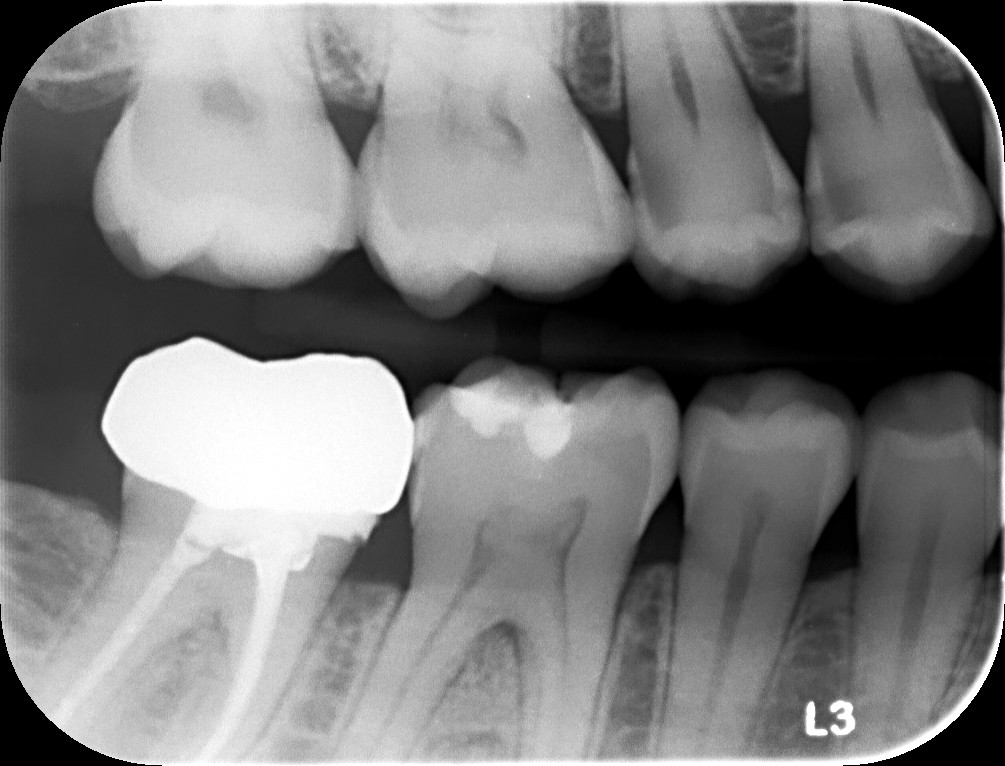

Le radiografie dentali sono uno strumento diagnostico imprescindibile in odontoiatria moderna. Consentono di rilevare problemi che non sono visibili a occhio nudo, come carie profonde, infezioni, alterazioni dell’osso e problematiche parodontali.

- Carie nascoste: individuazione di carie tra i denti o sotto restauri esistenti

- Valutazioni implantari: pianificazione precisa della posizione degli impianti dentali

- Parodontologia: controllo dello stato dell’osso e dei tessuti di supporto dei denti, fondamentale per prevenire e trattare le malattie gengivali (keyword ampliata)

- Controlli ossei e infezioni: rilevazione di granulomi, cisti o perdita ossea

- Elevata precisione diagnostica: immagini dettagliate che permettono interventi mirati